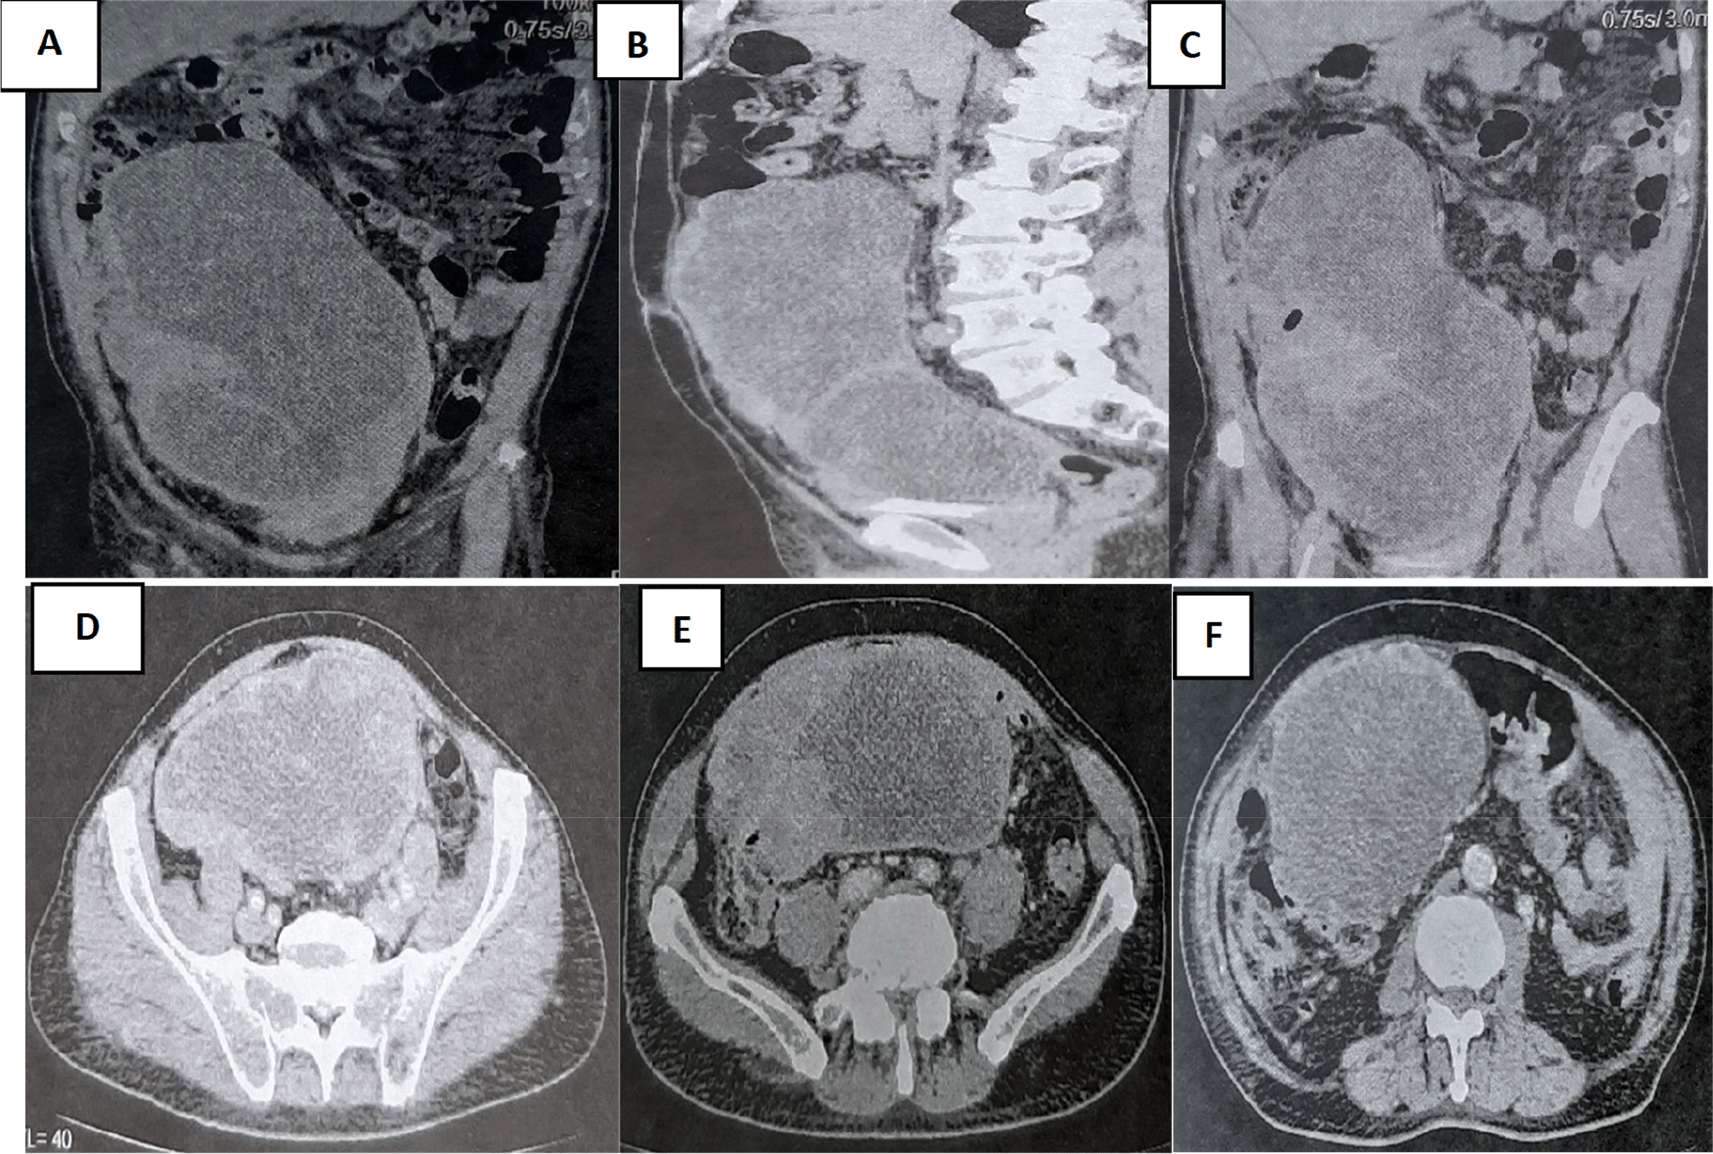

A 79-year-old White retired school-teacher male was admitted complaining of asthenia and diffuse abdominal pain. The patient had no notable pathological history and had never been operated on. The patient also had no familial pathologic history notably no cancer history. The physical examination revealed a large, solid pelvic mass extending to the epigastrium, which was responsible for abdominal pain and a feeling of tightness ( Figure 1).

A colonoscopy was performed but was incomplete due to the presence of an impassable stenosis at the sigmoid, which seemed to be extrinsic. An abdominal-pelvic CT scan was performed and described a large abdominal-pelvic mass of 25 cm in length, which was enhanced after injection of contrast product and seemed to have a digestive origin ( Figure 2).

Laparotomy confirmed the presence of a voluminous mass of the sigmoid adhering and invading the bladder dome extended to the upper rectum. This mass was friable, necrotic in places and centered by a liquefied hematoma ( Figure 3).